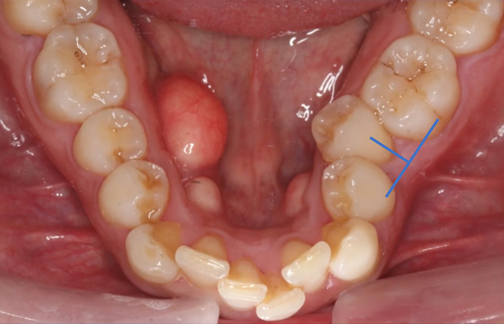

Four adult patients, seen by four different clinicians presented for orthodontic treatment with new orthodontic diagnostic terms of maxillary and mandibular hypoplasia with localized Orthodontosis and Orthodontitis (Figures 4–7),30 were successfully treated with the patented systems of FASTBRACES® Technologies. It is important to note that the universal orthodontic goal and accompanying treatment should be to successfully treat the biologically based diagnosis of the alveolar bone clinical morphology within a patient’s natural stable occlusion and morphologic appearance. Figure 4 holds particular significance as it sheds light on the complex nature of periodontal conditions, which involve multiple critical parameters. Notably, it reinforces the existing literature by demonstrating that the microbial flora surrounding tooth #25 or in an area already compromised by alveolar hypoplasia can progressively and rapidly deteriorate the alveolar bone.

Figure 4A Before Maxillary and Mandibular Orthodontosis and Orthodontitis of anterior teeth with localized severe gingival recession. The recession of #24 may be due to hypoplasia of #23 and #25 due to the fact that alveolar bone was not enough to sustain soft tissue coverage of #24.

Figure 4B Brackets are placed on lingually inclined mandibular teeth to facilitate alveolar bone restoration which in turns promotes the creation healthy soft tissue and the elimination of the hypoplasia (Orthodontosis). Note that brackets are not placed on labially positioned mandibular teeth.

Figure 4C Bracket placement on all teeth as previously lingually inclined roots are orthoerupted (man-made eruption).

Figure 4DAfter resolution of Maxillary and Mandibular Orthodontosis and Orthodontitis with restored alveolar bone and gingival architecture.